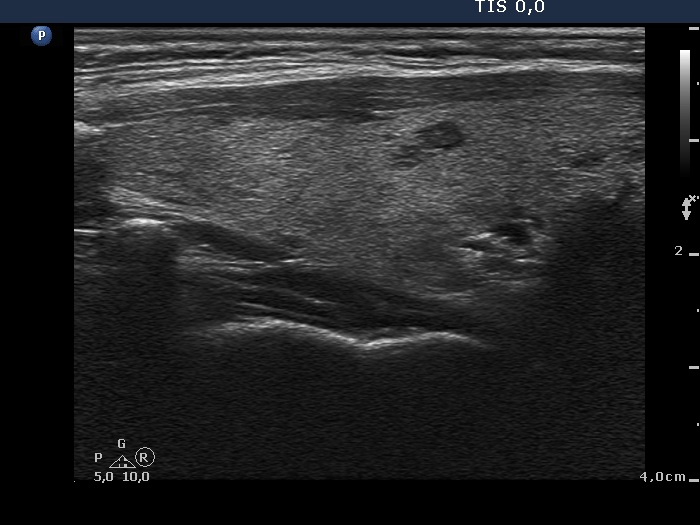

Consecutively operated patients with autoimmune thyroid disease - case 58 (1764) (ultrasonographic picture 5)

The patient is euthyroid without thyrostatic therapy

Left lobe, longitudinal scan.